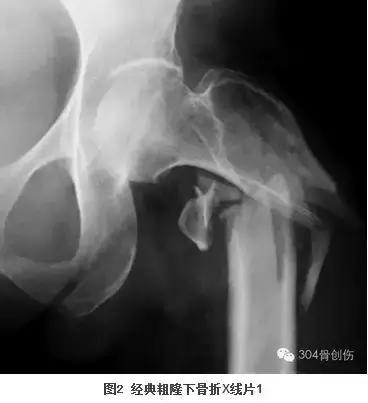

大查房见到一女性病人,57岁,洗澡时地滑导致股骨粗隆下骨折。粗隆下骨折多见于青壮年高能量外伤后,而眼前的病人是一位白净的中年女性,仅仅是洗澡过程中骨折,按说致伤能量不是很高,当时首先想到的是肿瘤骨转移的病理骨折,反复查看X线片和CT后不符合肿瘤骨转移病理骨折。王晓宁主诊医生再次补充病史:患者因内科疾病长期服用激素。服用激素能够导致骨坏死和骨质疏松,骨坏死常见于股骨头,骨质疏松骨折多见于股骨近端。带着疑问全科医生仔细阅读影像资料料,此例粗隆下骨折表现的仅是简单骨折(图1),而经典的粗隆下骨折多是粉碎或长螺旋形(图2、3)。全科医生畅所欲言,充分发表各自看法,却不能完美解释上述疑问,按现有医疗水平处理此类骨折不是难事,但解除不了内心的疑惑。经过激烈讨论后,决定暂缓手术、寻找证据、明确骨折原因。大家分头查找文献,两天后再次讨论。

2013年和1014年美国骨与矿物质研究学会(The American Society for Bone and Mineral Research,ASBMR-图10)对于完全及不完全非典型股骨骨折定义如下(图11):主要特点包括(1)此类骨折无明显创伤史;(2)骨折线起自外侧骨皮质并基本与股骨呈垂直走向;(3)完全性骨折贯穿两侧骨皮质,而不完全骨折只涉及外侧骨皮质;(4)骨折非粉碎性或微粉碎性;(5)骨折区域出现局部增厚的骨膜或骨内膜,非典型股骨骨折应满足以上4 条或以上才可定义为非典型股骨骨折。其次,次要特点不是非典型股骨骨折必须满足:(1)股骨干骨皮质厚度广泛增厚;(2)单侧或双侧前驱症状,如腹股沟或大腿的钝痛或酸痛;(3)双侧完全或不完全性股骨干骨折;(4)延迟愈合。